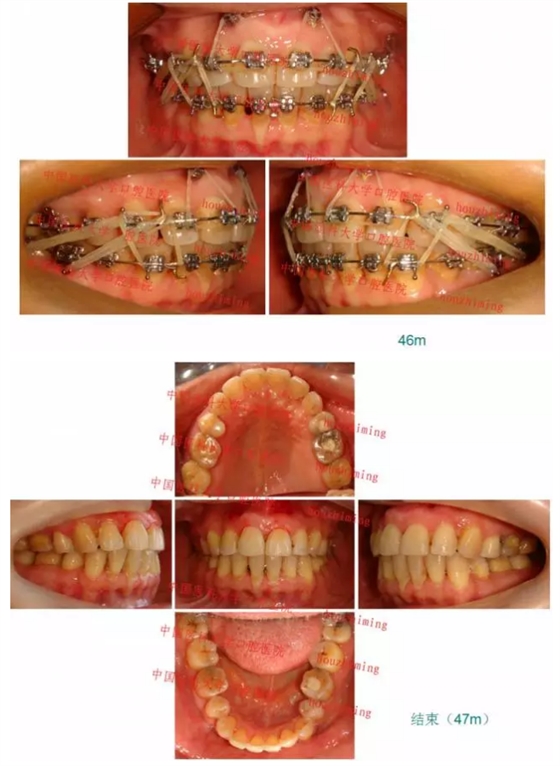

【原創(chuàng)博客】這樣的代償矯治大家滿意嗎?(重度骨性二類)——侯志明